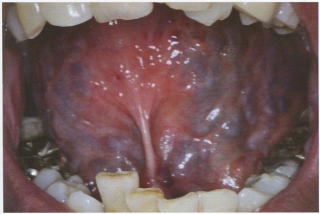

■舌下静脈の怒張=血瘀

重症例では舌下に下肢静脈瘤のような瘤が出来る。これは舌下の血絡といいます。

紫暗舌、瘀点、瘀班は同じ理由(血液の流れの滞り)で起こります。紫色の点、斑で表面が盛り上がってないもの。